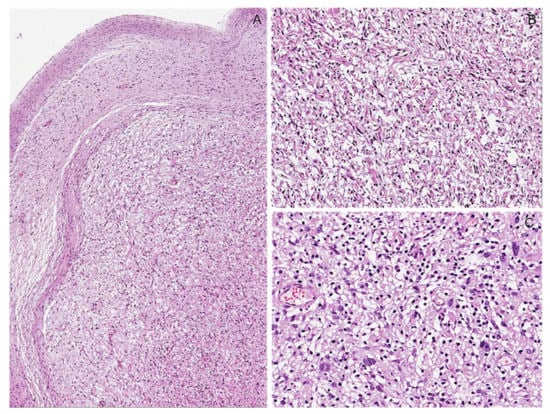

6.1. Classic Schwannoma

Immunohistochemical Features

6.2. Schwannoma with Degenerative/Ancient Changes (“Ancient Schwannoma”)